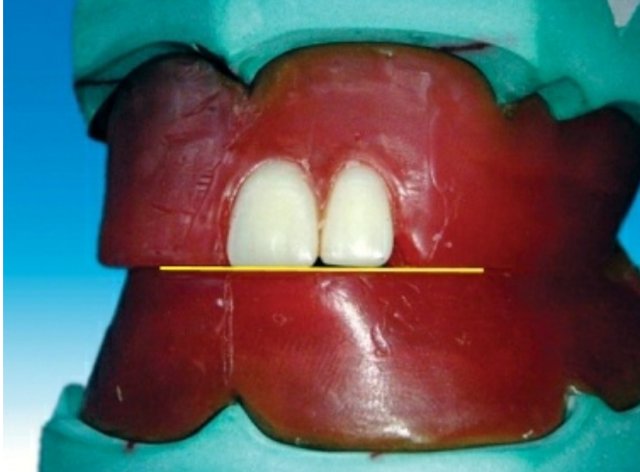

Placement of the maxillary central incisor in relation to all three planes.

🔻The long axis of the central incisor (the blue line) is positioned parallel to the

vertical axis (the red line) when viewed from the front

🔻The incisal edge of the maxillary central incisor is positioned in line with the

anterior occlusal plane . The central pin of the articulator will point the mesioincisal line edge of the central incisor.

🔻The central pin of the articulator will

point the mesioincisal line edge of the central incisor.

When viewed from:

Front: Long axis parallel towards the vertical axis.

Side: Slopes labially about 15 degrees.

Occlusal plane: Incisal edge is in contact with occlusal plane